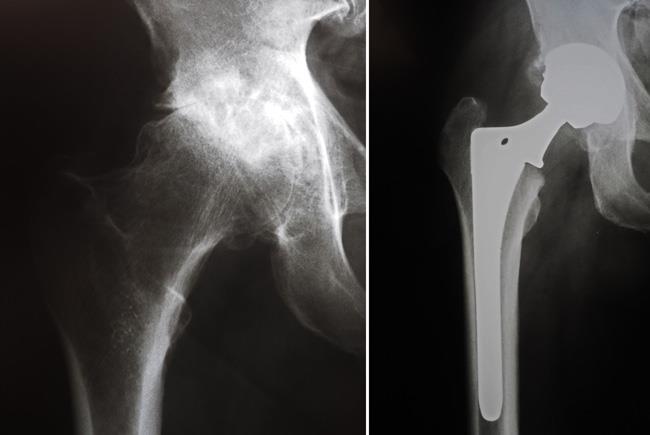

X-rays before and after total hip replacement. In this case, non-cemented components were used.